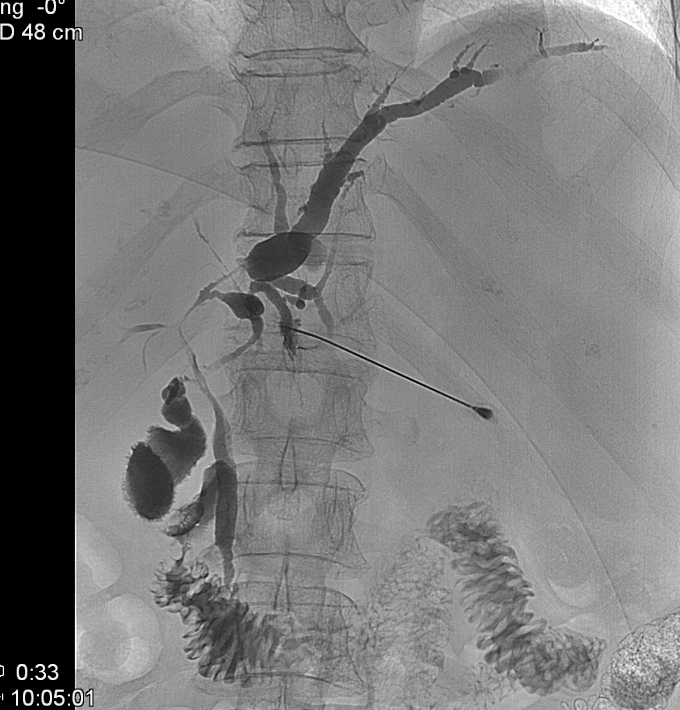

14.1.1.7. Percutaneous transhepatic cholangiography (PTC)

The percutaneous contrast filling of the biliary ducts can be necessary if no reassuring diagnosis was made by US, CT or MRI scans, or the ERCP implementation was unsuccessful due to a technical obstacle (Billroth II. gastric resection, choledochojejunostomy), or the canulation of the papilla of Vater was technically failure. PTC can be only performed in case of appropriate bleeding or coagulation status. (Figure 9) .

Figure 9: PTC (Percutaneous transhepatic cholangiography)

Significant amount of free abdominal fluid is also a relative contraindication. In the course of PTC, the liver punction is usually performed in the 9th or 10th rib spaces under fluoroscopic guidance using a 22 G Chiba needle. The punction should be guided towards the liver hilum. US guidance is helpful in the easier puncture of dilated or even peripherially located biliary ducts. The entire biliary system can be filled through this puncture. Following the diagnostic biliary duct contrast administration – after a previous consultation – bridging of the detected biliary stenosis can be performed (PTC-PTD, biliary duct stenting). Moreover, percutaneous stone extraction can be carried out if necessary.